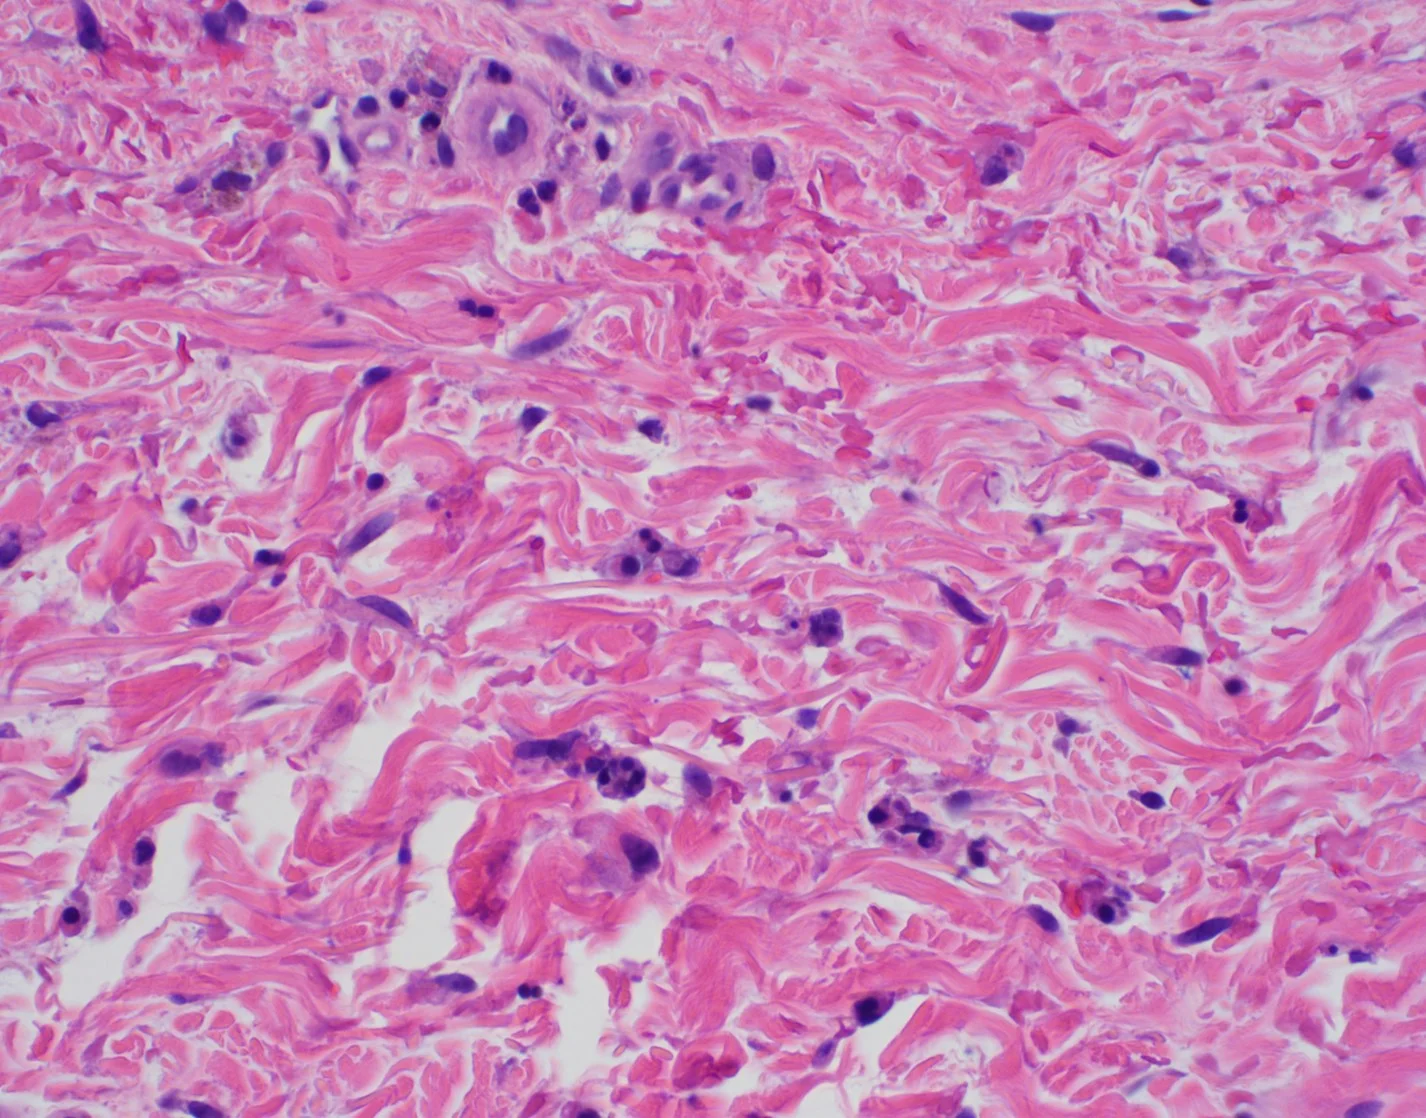

Case 6: A Case of Desmoplastic Malignant Melanoma: A Diagnostic Pitfall

Caregivers: Michael James Davis, BMus, Dipti Anand, MD; Atlanta, GA

History: A 66-year-old Caucasian woman presented for her routine physical examination and was found to have a lesion on her left upper arm. Physical examination and review of systems were otherwise negative.

Physical Exam: A 0.5 x 1.0 cm poorly defined, asymmetric pink plaque with irregular borders and subtle dotted vessels was present on the left upper arm. A shave biopsy with the clinical impression of basal cell carcinoma vs squamous cell carcinoma was performed.

Histopathology: Histology showed dermal scarring with stromal perivascular lymphocytic inflammation, and slight junctional melanocytic proliferation. S-100, Melan-A and SOX-10 immunohistochemical markers highlighted the patchy atypical junctional melanocytic proliferation, with S-100 and SOX-10 also showing focal and weak staining of the dermal spindle cells. Additional information revealed no prior history of biopsy at this site. The pathology was signed out as “atypical compound melanocytic proliferation with scar” with recommendation for complete removal of the lesion and correlation with the residuum in the re-excision specimen.

A full thickness re-excision of the site showed, in association with scar of the previous procedure, classic appearing melanoma in-situ with lentiginous, contiguous junctional melanocytic proliferation of single and nests of enlarged, atypical melanocytes. In the dermis was a diffuse proliferation of cytologically banal, delicate spindle cells with mildly enlarged and slightly hyperchromatic nuclei and occasional dermal mitoses (~2/mm2). Associated trailing lymphoid aggregates were noted in the stroma. S-100 and SOX-10 diffusely highlighted the dermal melanocytic proliferation which was negative for Melan-A.

Diagnosis: Invasive Malignant Melanoma, Desmoplastic type, with a Breslow thickness of 2.1 mm, Clark’s level 4, and with a pathologic tumor stage of pT3a.

Points of Emphasis: Desmoplastic Melanoma (DM) is a rare cutaneous malignancy that proves a challenge for both clinicians and pathologists because of its subtle presentation and broad differential diagnosis. It is typically found on chronically sun-damaged skin of older individuals and has a male to female ratio of approximately 2:1. DM often presents as an amelanotic plaque or an ill-defined scar-like lesion that lacks an epidermal component; it can also be found in the background of other melanomas, most commonly lentigo maligna melanoma. Compared to conventional melanoma, DM has both a lower rate of nodal metastasis despite greater median tumor thickness at presentation and a relatively higher incidence of local recurrence.

Histologically, DM remains a challenging diagnosis and necessitates a high index of suspicion. Atypical spindle cells are found in a densely hyalinized collagenous stroma. There can be deep infiltration and invasion into the subcutis, and DM has a high propensity for perineural invasion. Trailing lymphoid aggregates can be a subtle clue in reaching the diagnosis. An important pitfall to appreciate is that DM can be negative for melanocytic markers including Melan-A, Mart-1, and HMB-45. In this case, the tumor was negative for Melan-A.